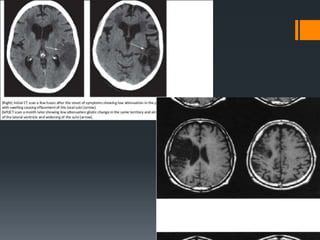

INVESTIGATIONS

Carotid duplex

CT Scan

Electrocardiogram

MRI Scan

Cerebral arteriogram